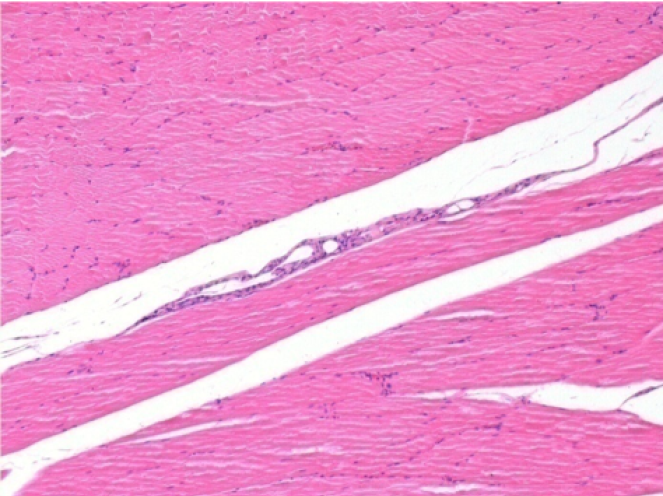

3 months (D90)after Endopeel Injection 0.1ml in the right pretibial muscle.

7 months (D210)after Endopeel IM Injection 0.1ml in the right pretibial muscle.

Complete Restitutio ad integrum after 7 months